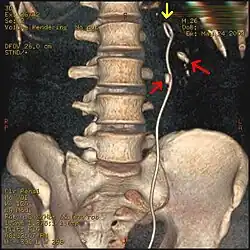

De katheter, ook wel stent genoemd, heeft aan beide uiteinden een krul of J-vorm (dus een dubbele J) waardoor hij op zijn plaats blijft. In beide krullen bevinden zich gaatjes waardoor urine in en uit het buisje kan stromen. De vorm verklaart de naam van het instrument. De katheter wordt met behulp van een cystoscoop door een uroloog in de urineleider geplaatst. Door het afvloeien van in de nier opgehoopte urine wordt de pijn meteen verlicht.

Een dubbel-J-katheter wordt door de uroloog door middel van een cystoscopie geplaatst in de urineleider, zodanig dat het ene uiteinde in het nierbekken ligt en het andere uiteinde in de blaas. Eventueel maakt men daarbij gebruik van doorlichting, al of niet met gebruik van contraststof.

Bij een eventuele vergruis-behandeling heeft de katheter als voordeel dat door een aanwezige metaalfilm op een röntgenfoto de exacte locatie van de niersteen goed te zien is.